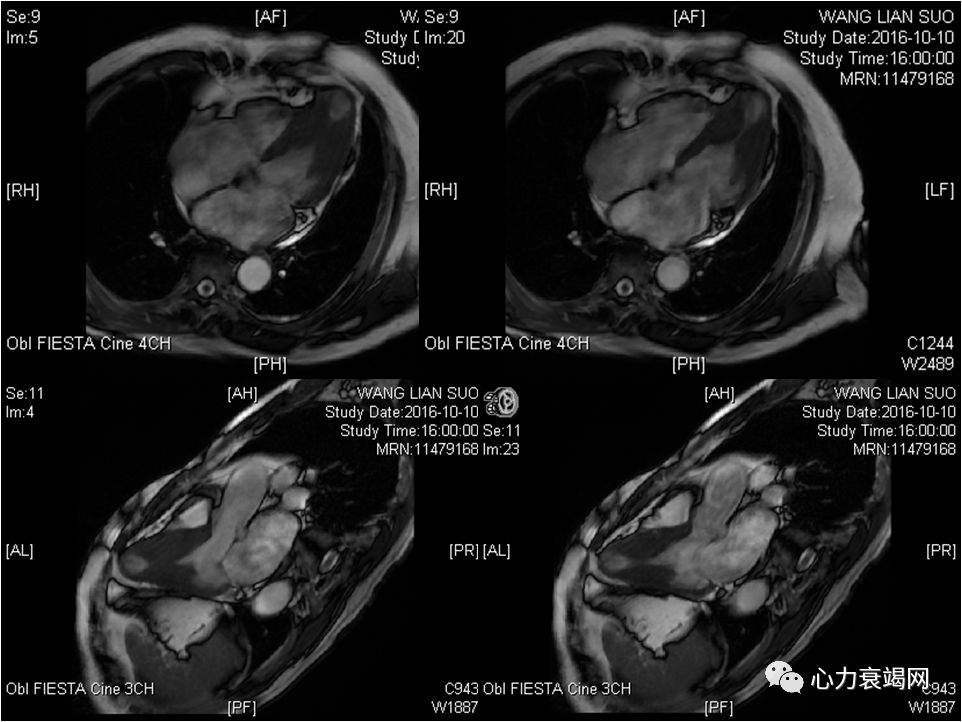

左房内径轻度增大,左室腔正常高限

左室室间隔中远段及侧壁中段室壁增厚,致左室中部梗阻(最厚约19~20mm)

心尖部室壁变薄,可见矛盾运动

余左室壁各节段收缩运动大致正常,舒张轻度受限

左室流出道收缩期末未见明确梗阻征象,左室中部梗阻

延迟增强后心尖部可见明显透壁样强化

右房增大,右室不大

印象:肥厚性心肌病,左室心尖部室壁瘤形成